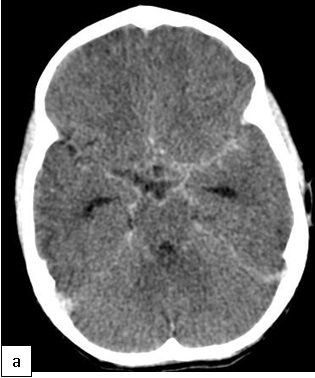

On cranial CT, PML lesions may appear as hypodense patchy or confluent white matter regions. Typical MRI features include single or multiple non-enhancing, non-space-occupying, predominantly white matter lesions commonly involving the frontal and parieto-occipital subcortical white matter.